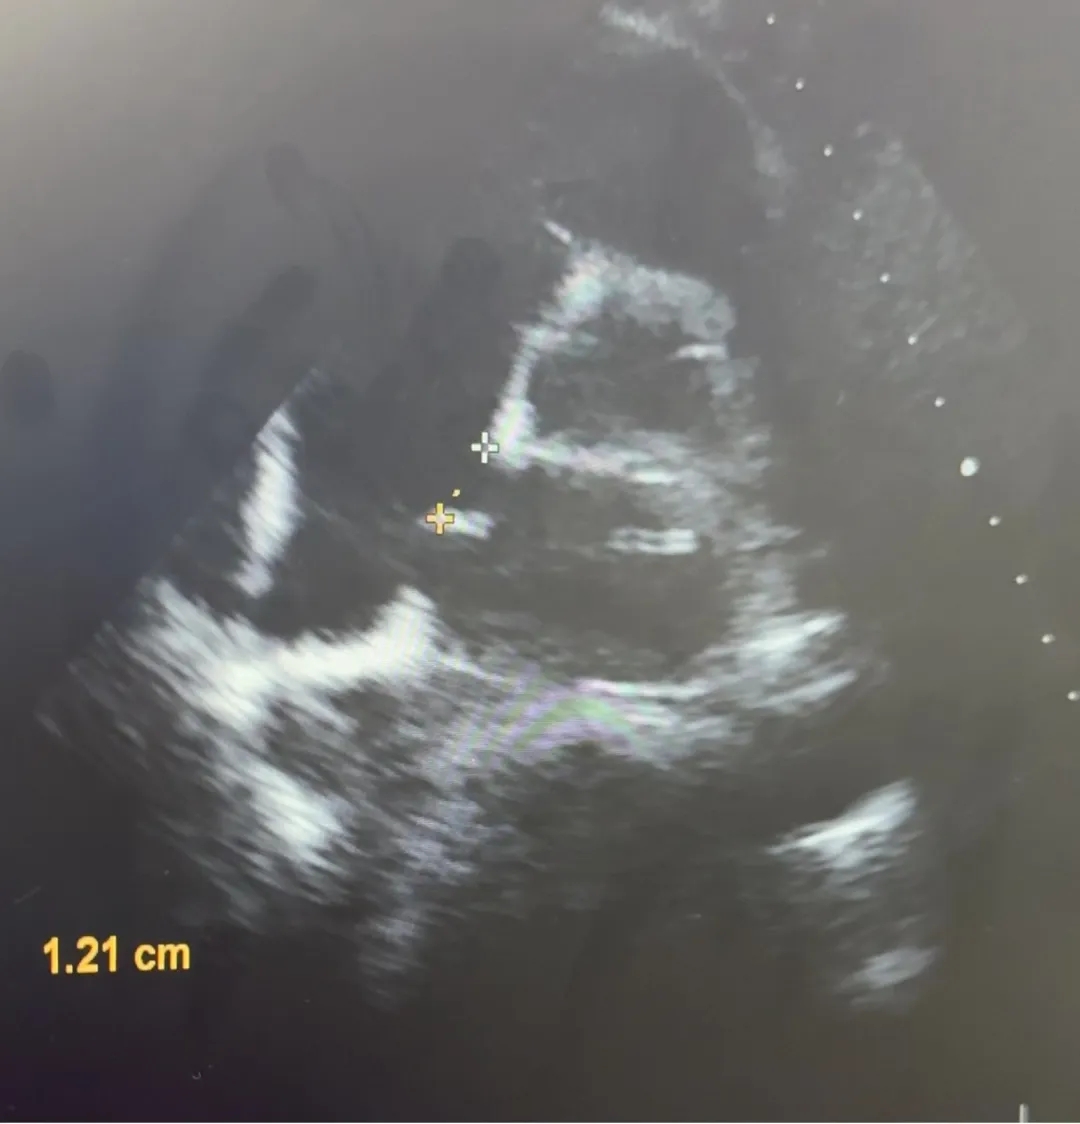

本例患者术前心脏彩超提示,四腔心切面断口大小10.8mm,短轴切面断口大小11mm,术中复测,主动脉短轴切面缺损12.1mm,缺损旁合并房间隔膨出瘤,其房间隔膨出瘤位置较薄弱、边缘偏软,主动脉短轴切面测量其缺损合并ASA为23.0mm,四腔心切面测量其缺损合并ASA为24.7mm,综合考虑使用BDASD-I-30规格生物可降解ASD封堵器,16F可降解输送系统进行封堵。

主动脉短轴切面

缺损12.1mm